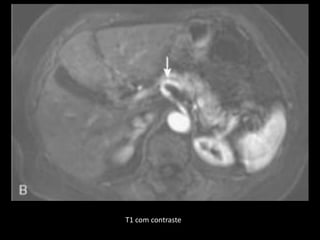

T1 com supressão de gordura

T1 com contraste

T1 com contraste: realce intenso e eliminação

rápida;